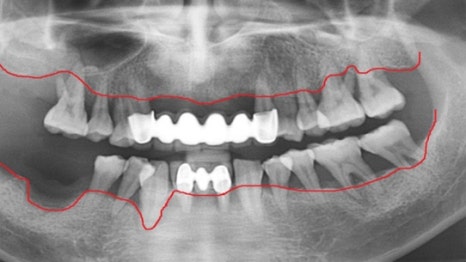

사례 1

과잉진료 없이 꼭 필요한 임플란트만 식립

다른 치과에서 6개 치아 발치 후 12개 임플란트를

권유받았던 환자분이 내원하셨습니다.

연세고운미소치과에서는 레이저 치주 치료를

진행하여 치아를 살리고, 최종적으로 6개의

임플란트만 식립하여 치료를 마무리했습니다.